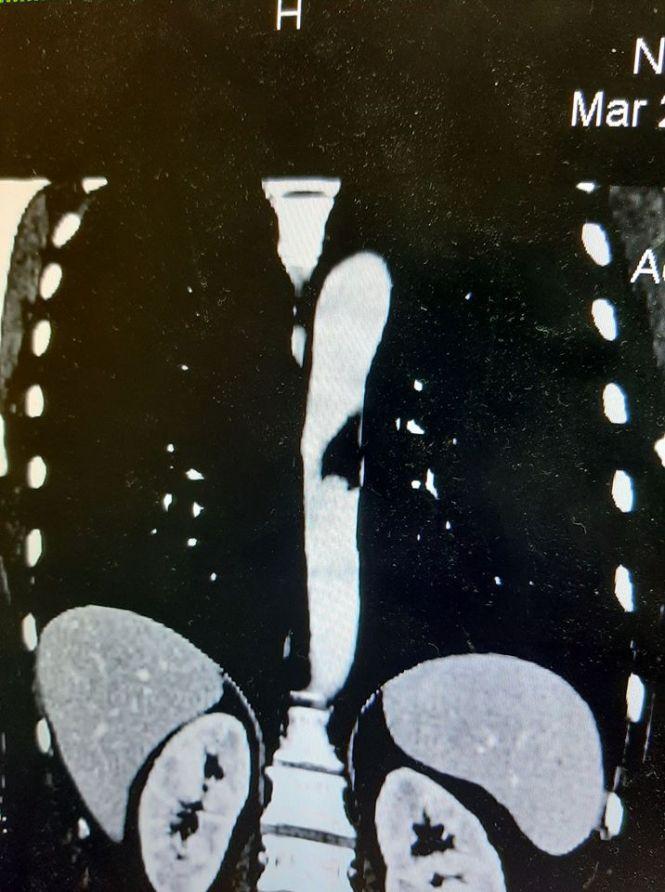

45-річна тернополянка звернулася в лікарню з діагнозом симптомний тромб грудного відділу аорти, який ускладнився відривом частинки тромбу та оклюзією термінального відділу аорти тромбом-емболом, йдеться на сайті Тернопільської університетської лікарні.

- Як правило, тромб на здоровій судині не буває, тому ми запідозрили, що під ним є якась тріщина чи надрив інтими (внутрішньої оболонки артерії, – ред.), – розповідає завідуючий відділенням інтервенційної радіології Богдан Маслій. Ускладнювалася операція ще й тим, що тромб знаходився в порожнині грудної аорти, а тому проводити відкриту операцію було занадто ризиковано. – Найбільш оптимальним варіантом у таких випадках є ендоваскулярне ендопротезування за допомогою стент-графту (металевий каркас, вкритий синтетичною мембраною, – ред.). Ми ідеально підібрали розмір стент-графту. Саме такий розмір був наявний у Чернівецькому кардіодиспансері. По передачі між двома лікувальними закладами ми отримали цей пристрій та успішно його імплантували. Пацієнтці він дістався безкоштовно, адже придбаний по державній програмі, хоча його вартість при покупці пацієнтом у фірми-представника сягає в межах 10 тисяч доларів, – пояснює Богдан Маслій.

– Ми повинні були створити знижений серцевий викид на момент роздування стент-графту. Бо при високому тиску цей стент «здуває» в дистальні відділи аорти. Тому потрібно знизити тиск і серцевий викид. Ми виконали ще одне втручання, поставили тимчасовий кардіостимулятор, за допомогою якого могли керувати частотою серцевих скорочень та серцевим викидом. Крім того, катетеризували ліву підключичну артерію, вставивши туди катетер, який слугував маркером для позиціонування нашого стент-графту. Також через цей катетер контрастували аорту. Після цього, коли вже успішно встановили стент-графт, зробили ще одне контрольне контрастування стент-графту для перевірки успішності операції. Проте був момент, який нас лякав перед операцією найбільше, – це відрив тромбу після розкривання стент-графту. Тому ми перевірили гілки аорти – верхню брижову артерію та черевний стовбур і ниркові артерії. Це було ще одне інтервенційне втручання. На щастя, всі судини були вільні, тромб не відірвався. Тепер він знаходиться між стінкою судини та стент-графту. Фінальний етап – судинні хірурги зашили отвір у судині і надлишки протезу видалили. Рану зашили і поставили дренажі, – розповів про хід операції Богдан Маслій.